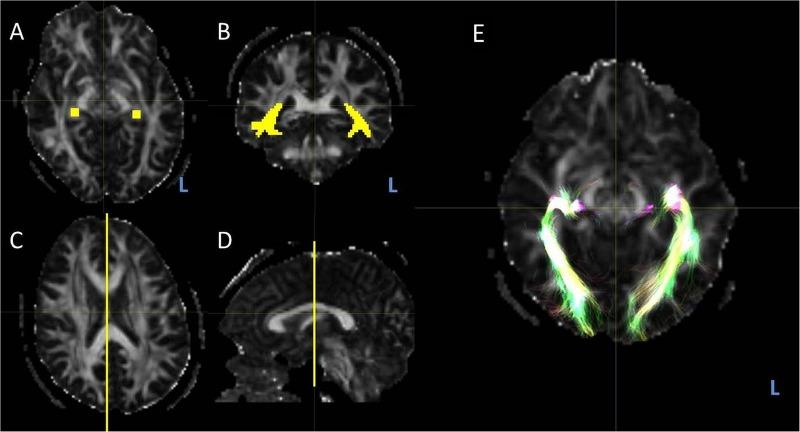

57 patients with epilepsy were identified with language functional MRI (fMRI) and diffusion MRI acquisition. Language lateralisation indices from fMRI(LI) and optic radiation and arcuate fasciculus probabilistic tractography was performed for each subject. The subjects were divided into left language dominant (LI>0.4) and non-left language groups (LI<0.4) according to their LI.

A negative linear correlation was identified between language lateralisation and MLA, with greater left lateralised language associated with more anteriorly placed left Meyer's loops (R value -0.34, p=0.01). There was a significant difference in mean MLA between the two groups, with the left loop being anterior to the right loop in the LI>0.4 group and posterior to the right loop in the LI<0.4 group (p=0.003). No correlation was found between language lateralisation and arcuate fasciculus volume.